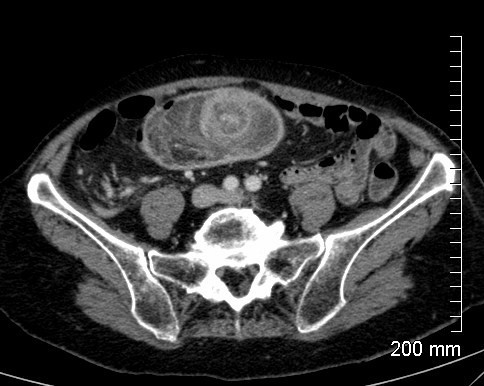

Q

Homme 50 ans, violentes douleurs abdominales et syndrome occlusif, un TDM est réalisé. Diagnostic?

A

Invaginaton Intestinale aiguë